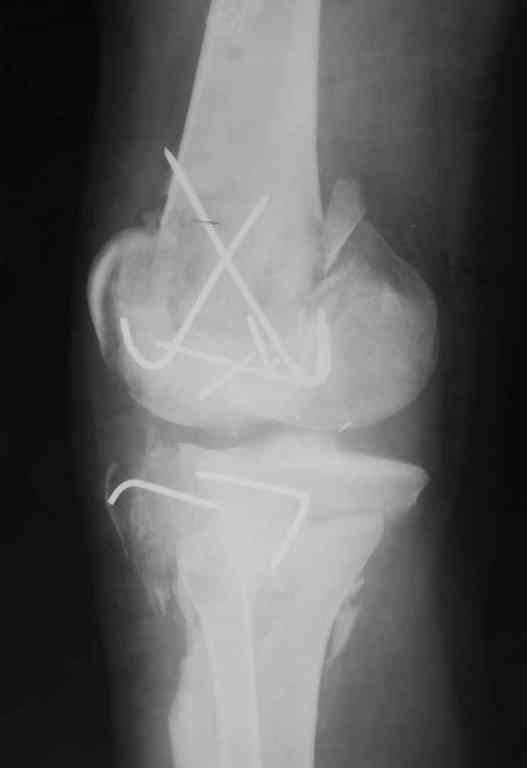

Пожалуйста, снимки.

Коллеги фиксатор Numelock II

На вашем снимке из-за ротации трудно угадать положение пластины, и желательно сделать снимок с захватом верхнего участка бедра.

Одинокий кортикальный шуруп не удержит тибиальный бугор, сустав тибиал плато оставлен без репозиции и фиксации.

Здесь применение материала Plexur http://www.plexur.com для пластики при дефектах кости у больной с огнестрельной раной латерального тибиал плато с повреждением малоберцового нерва. Несмотря на интактный медиальный мышелок, для профилактики от вальгуса установлен АВФ и сделана ангиограмма.

После нескольких обработок и вакуумирования, поэтапно сделана фиксация тибиального бугра шурупами. И окончательную фиксацию закончили латеральной пластиной для тибиал плато и установкой пластического материала.